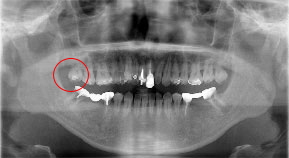

自家歯牙移植の症例

歯牙移植治療前 40歳代 女性

歯牙移植治療後